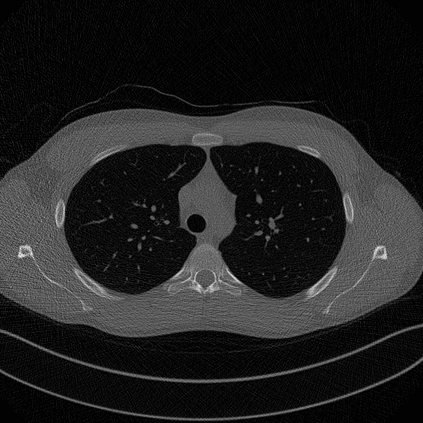

In this work, we present Eformer - Edge enhancement based transformer, a novel architecture that builds an encoder-decoder network using transformer blocks for medical image denoising. Non-overlapping window-based self-attention is used in the transformer block that reduces computational requirements. This work further incorporates learnable Sobel-Feldman operators to enhance edges in the image and propose an effective way to concatenate them in the intermediate layers of our architecture. The experimental analysis is conducted by comparing deterministic learning and residual learning for the task of medical image denoising. To defend the effectiveness of our approach, our model is evaluated on the AAPM-Mayo Clinic Low-Dose CT Grand Challenge Dataset and achieves state-of-the-art performance, $i.e.$, 43.487 PSNR, 0.0067 RMSE, and 0.9861 SSIM. We believe that our work will encourage more research in transformer-based architectures for medical image denoising using residual learning.